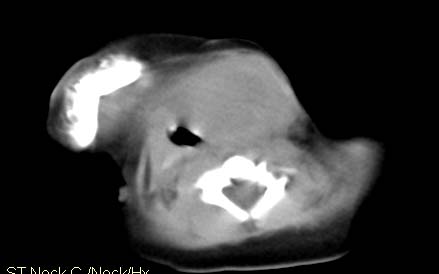

男,26天,发现左侧颈部包块5天,质较硬,患儿不哭不吵,无明显发热,头向右侧歪斜,其父母诉患儿出生时正常,昨天查血象wbc19.4×10的9次方/l,b超考虑来源于甲状腺的恶性肿瘤,我科认为肿块内有低密度区,而且病程发展较快,血象高,考虑炎性病变可能大。患儿年龄太小没做增强。请大家提出高见。

男,26天,发现左侧颈部包块5天,质较硬,患儿不哭不吵,无明显发热,头向右侧歪斜,其父母诉患儿出生时正常,昨天查血象wbc19.4×10的9次方/l,b超考虑来源于甲状腺的恶性肿瘤,我科认为肿块内有低密度区,而且病程发展较快,应该首先排除血肿,其次考虑感染

随访结果:炎症(患儿经过一星期抗炎治疗后颈部包块明显缩小,现已经正常)。